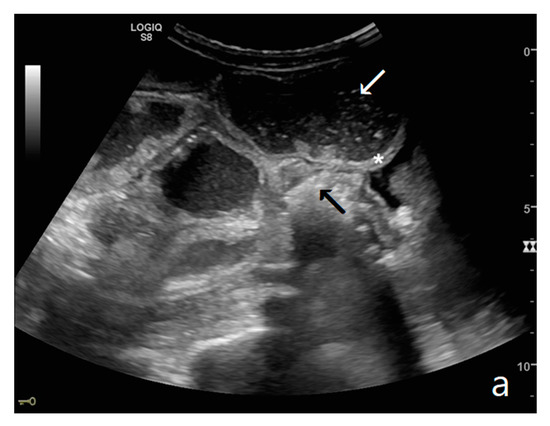

Figure 1.

(a,b). A simple SBO. Ultrasound images show fluid-filled, dilated small bowel loops (a,b) with hyper-kinesis and hyper-representation of valvulae conniventes (white arrow) (a); tail comet artifacts are visible due to air-fluid levels (dashed arrow) (b) and groups of bowel loops with severe differences in diameter (‘bowel jump diameter’) are evident more superficially (*) (b). No free fluid was detected in the abdominal cavity or between bowel loops.

Small bowel dilatation is defined as bowel diameter ≥2.5 cm measured from outer wall to outer wall [12,35,37]. At an early stage of the disease, the diameter should not be considered an absolute criterion for diagnosis, and other signs must be used: the bowel loop diameter at this stage could be within the normal range, but bowel loops are fluid-filled, hyperkinetic, and with plicar hyper-representation (Figure 1a and Figure 2a) [12].